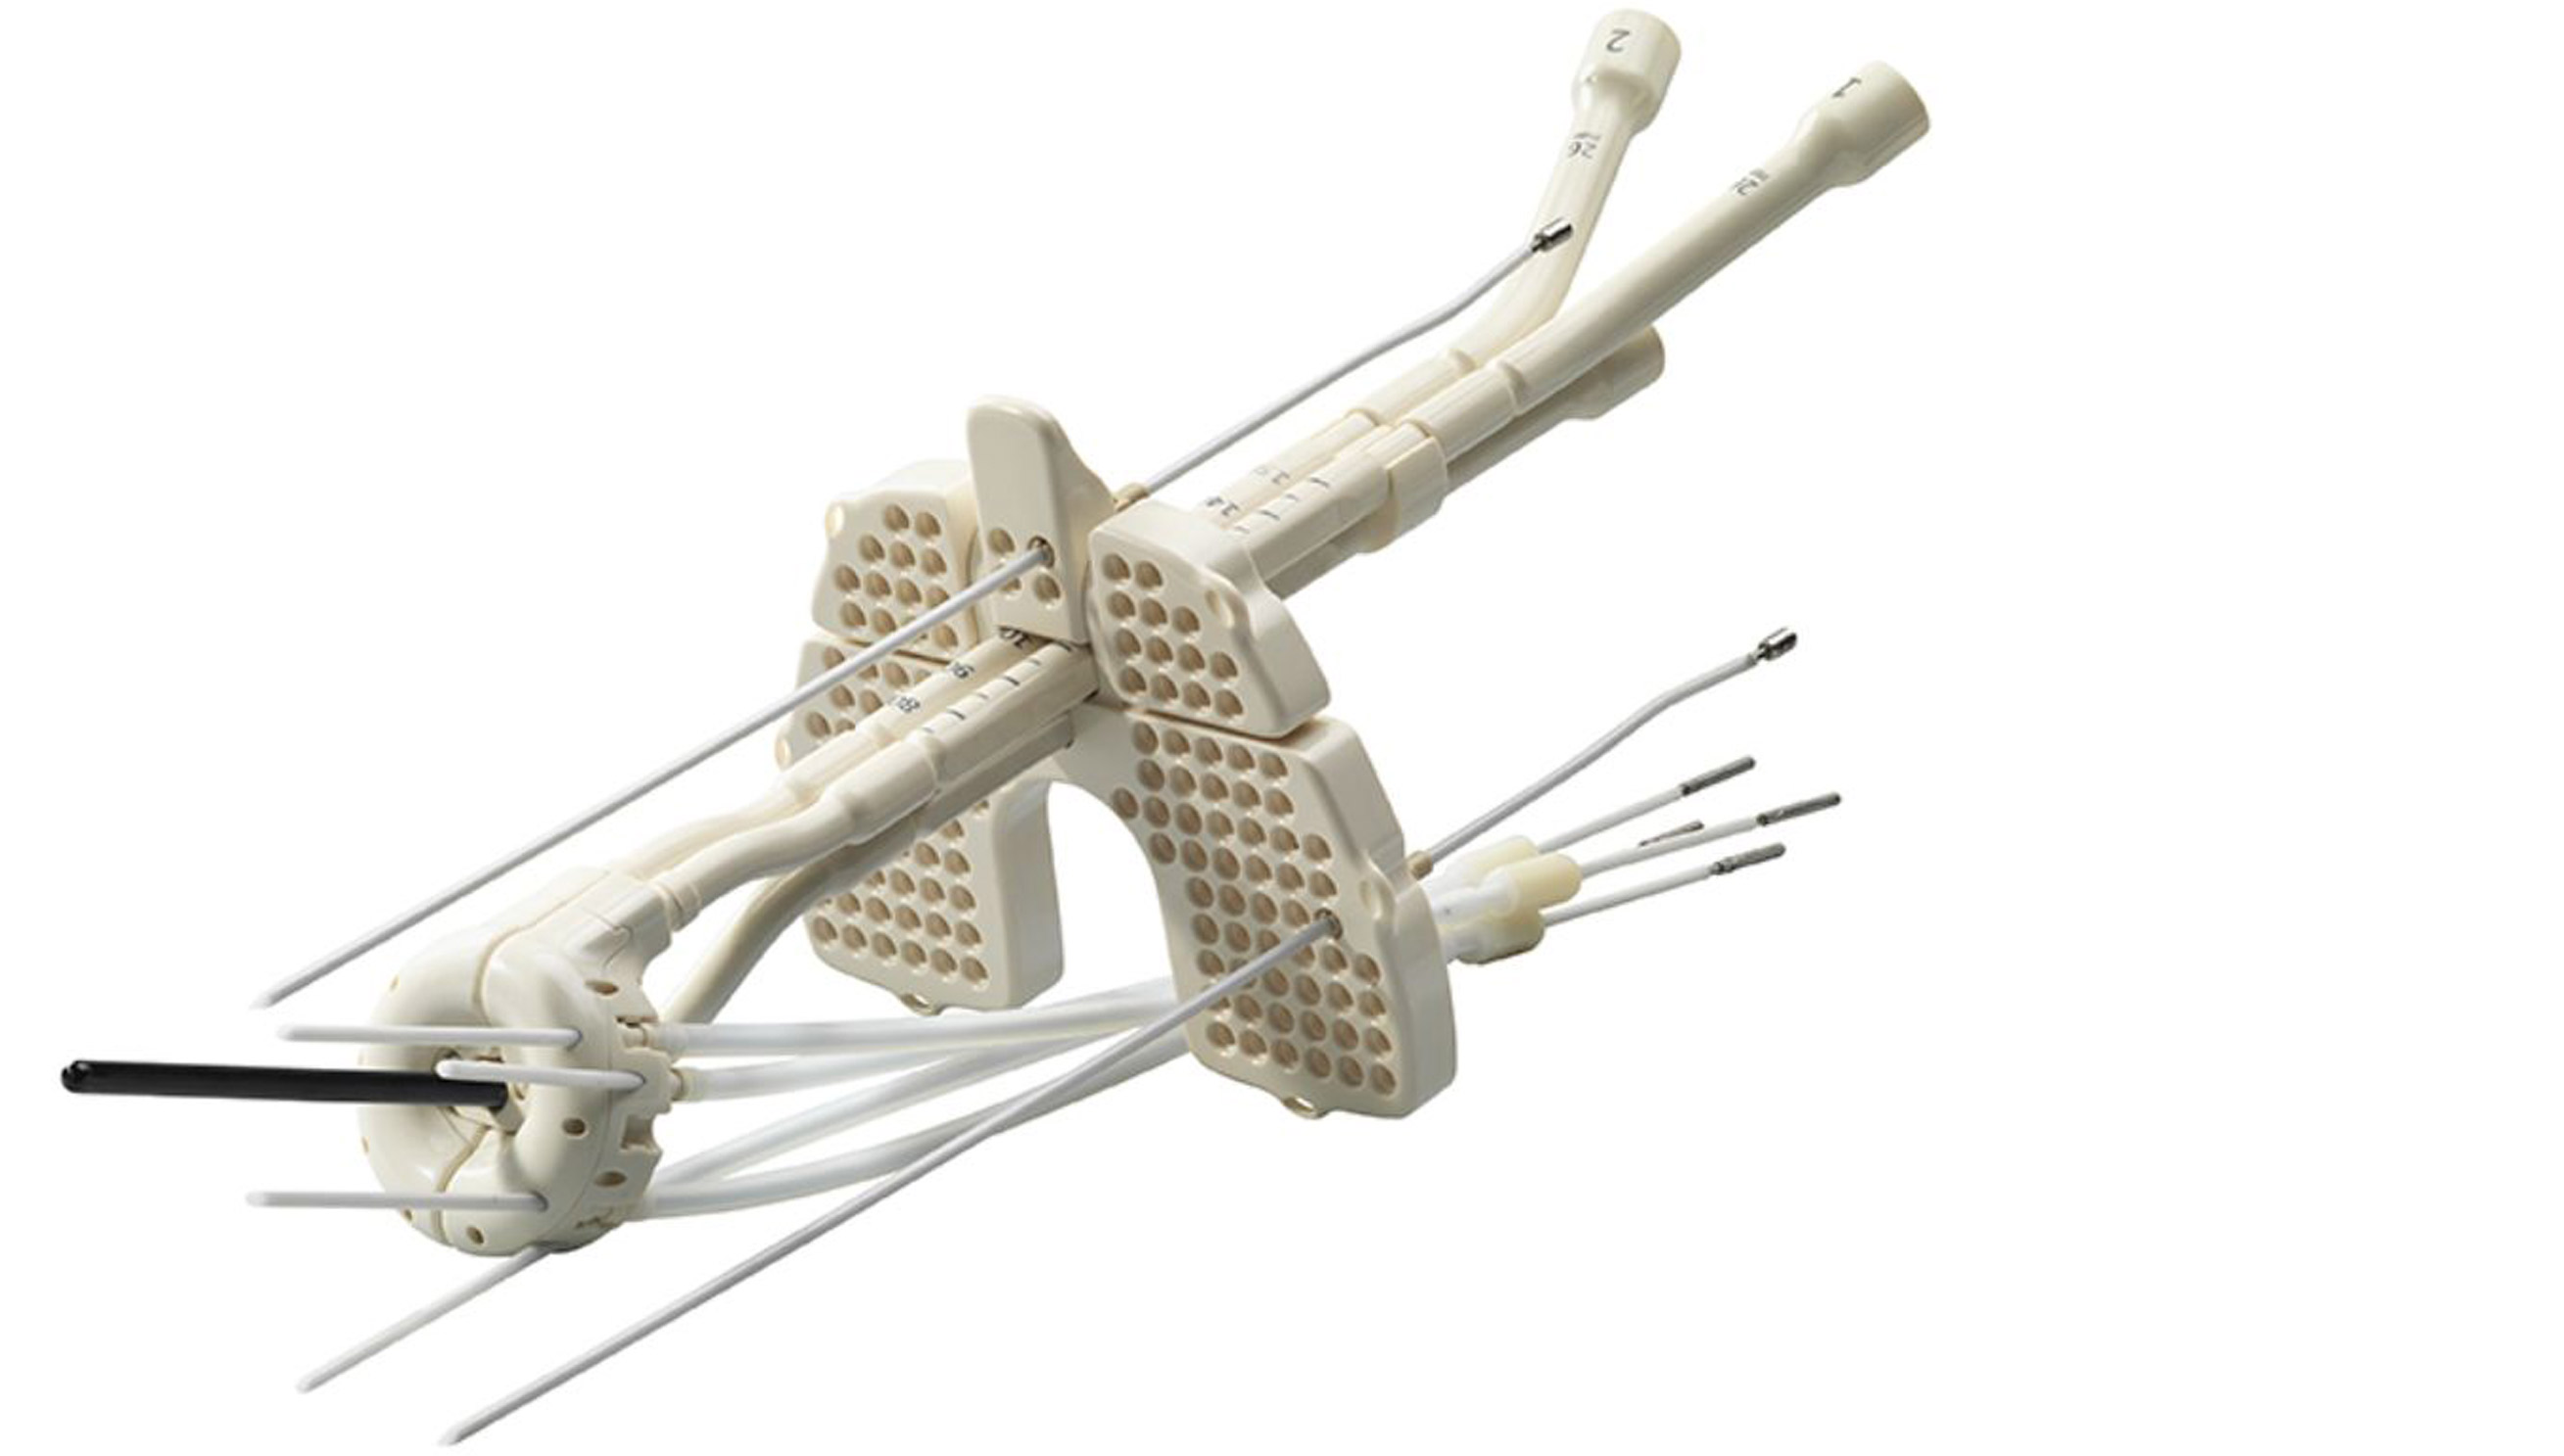

医科达为妇科近距离治疗提供了多种施源器,适用于从腔内到组织间插植等各种应用,可在妇科近距离治疗中提升更加精确的剂量杀死癌细胞。

could not find asset妇科施源器主要包括